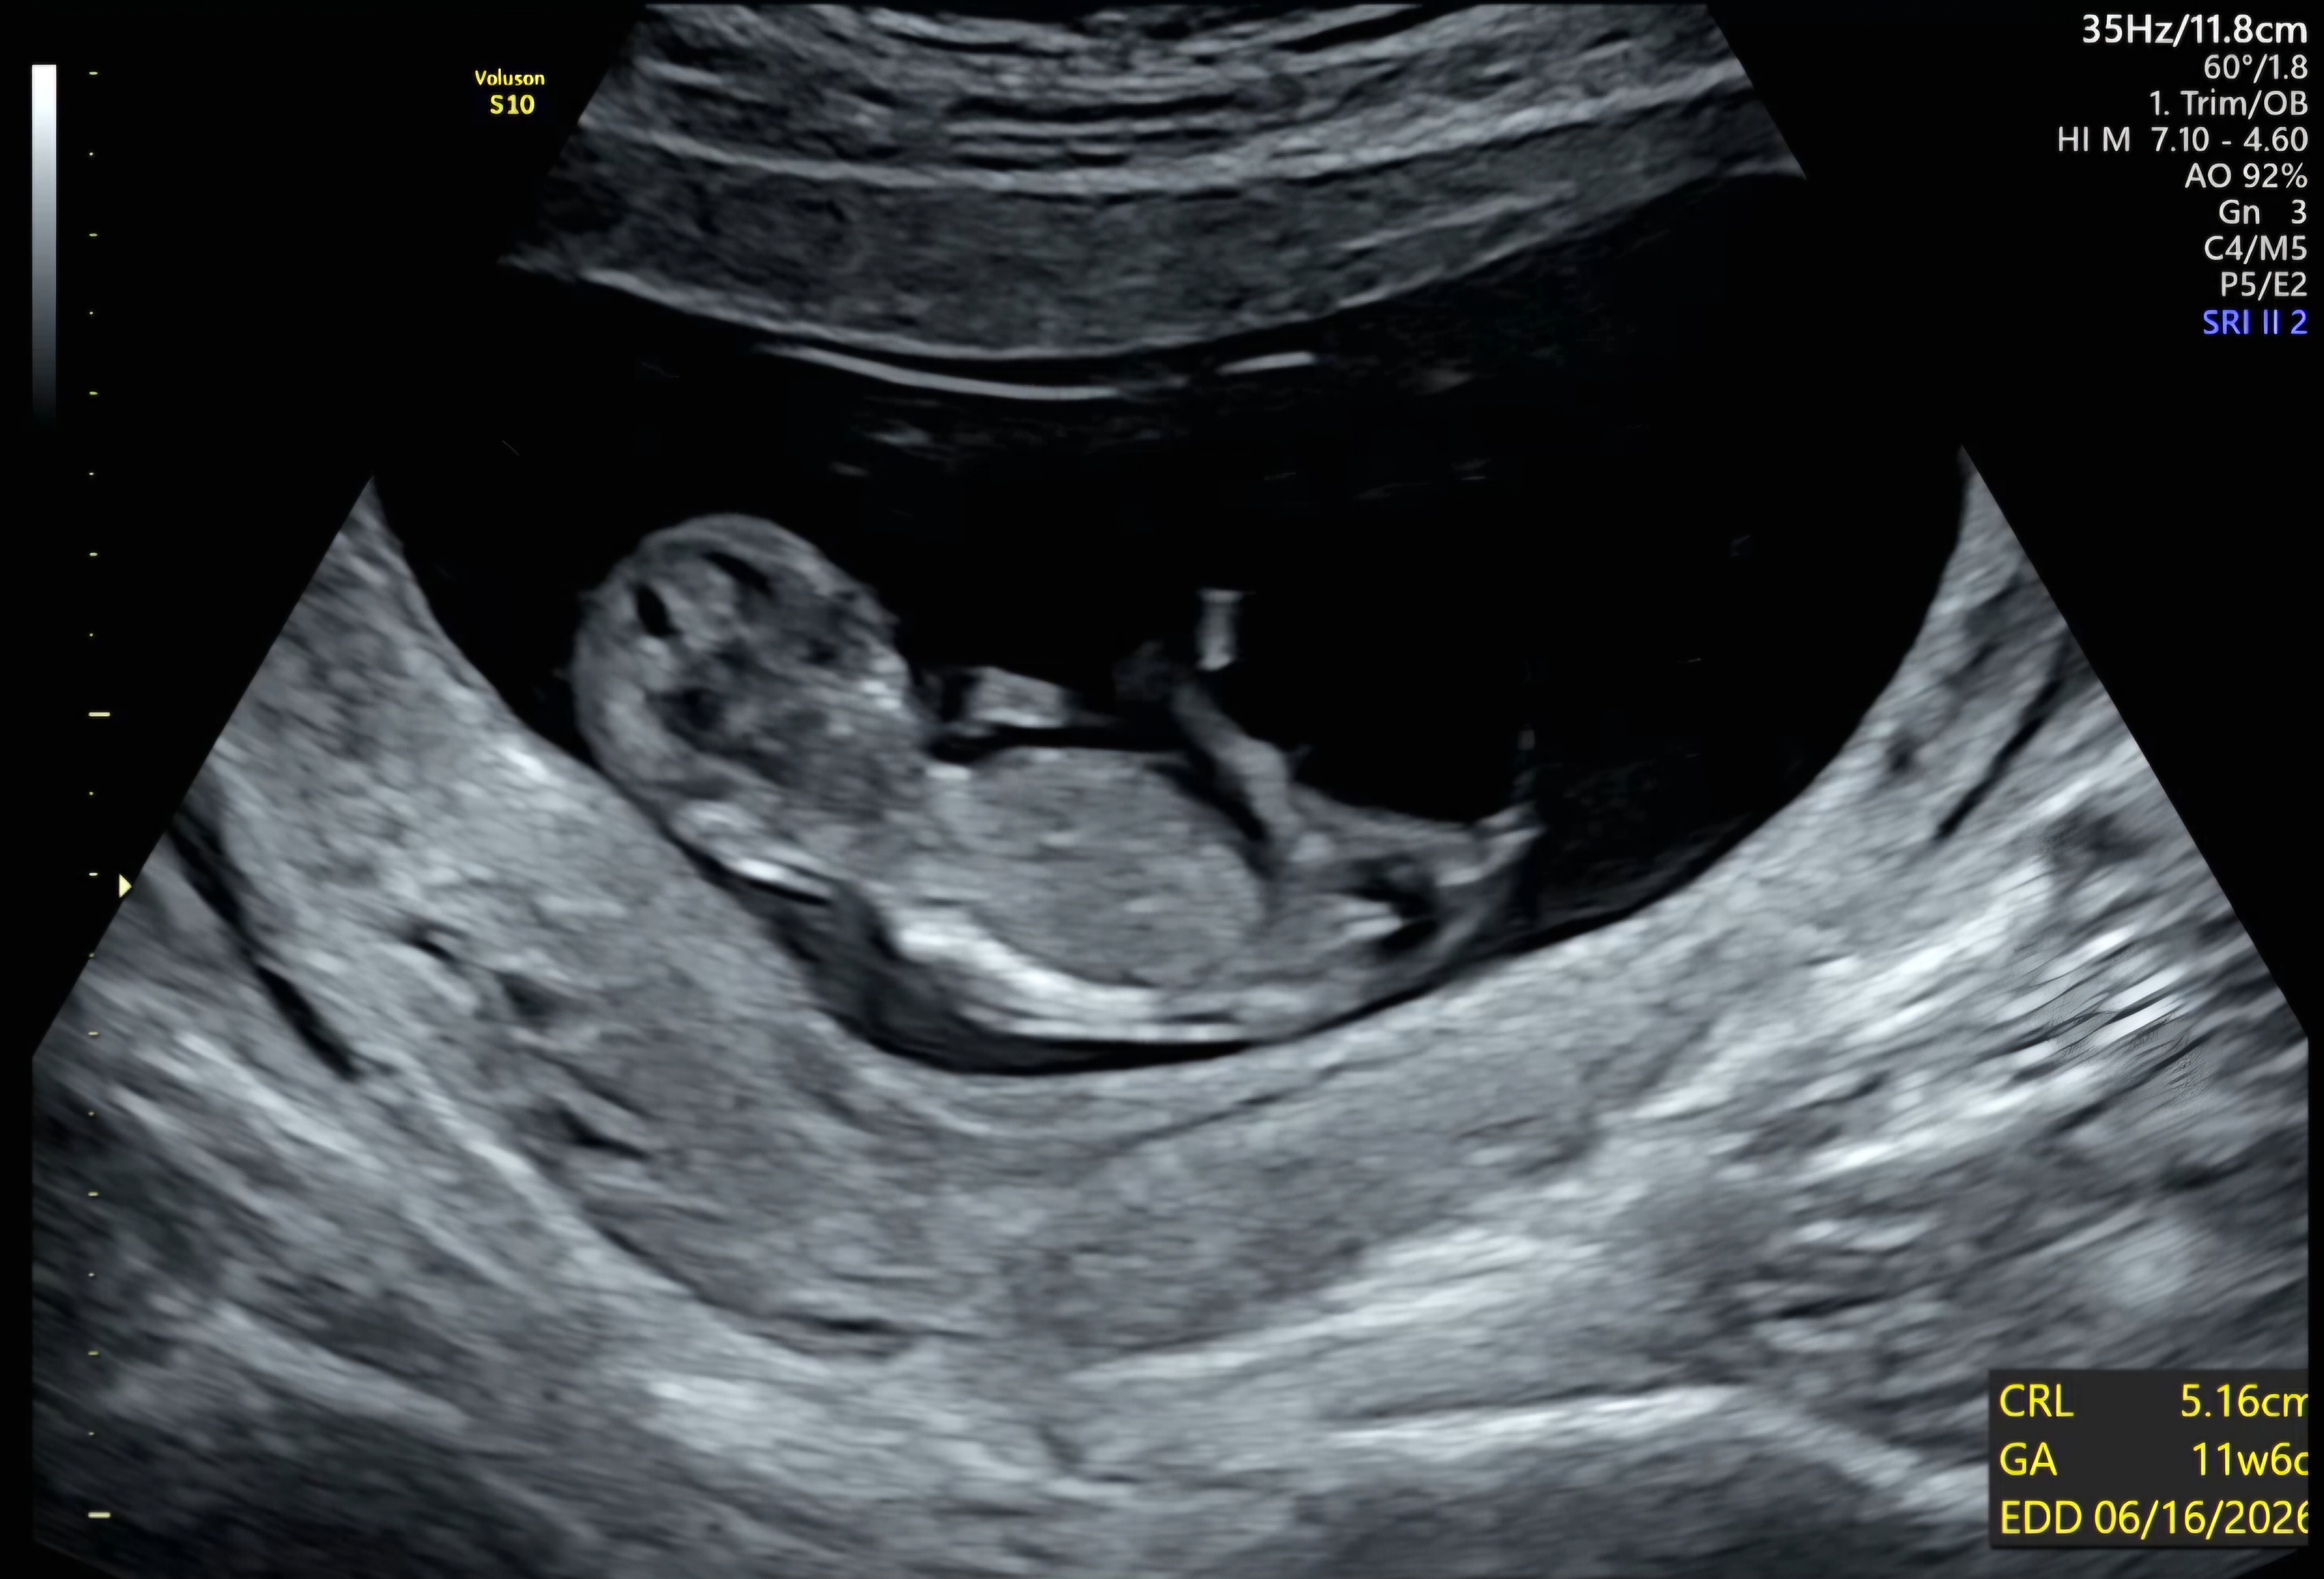

각도법으로 성별 맞춰주세요!

둘째인데 한번만 투표해주세요!